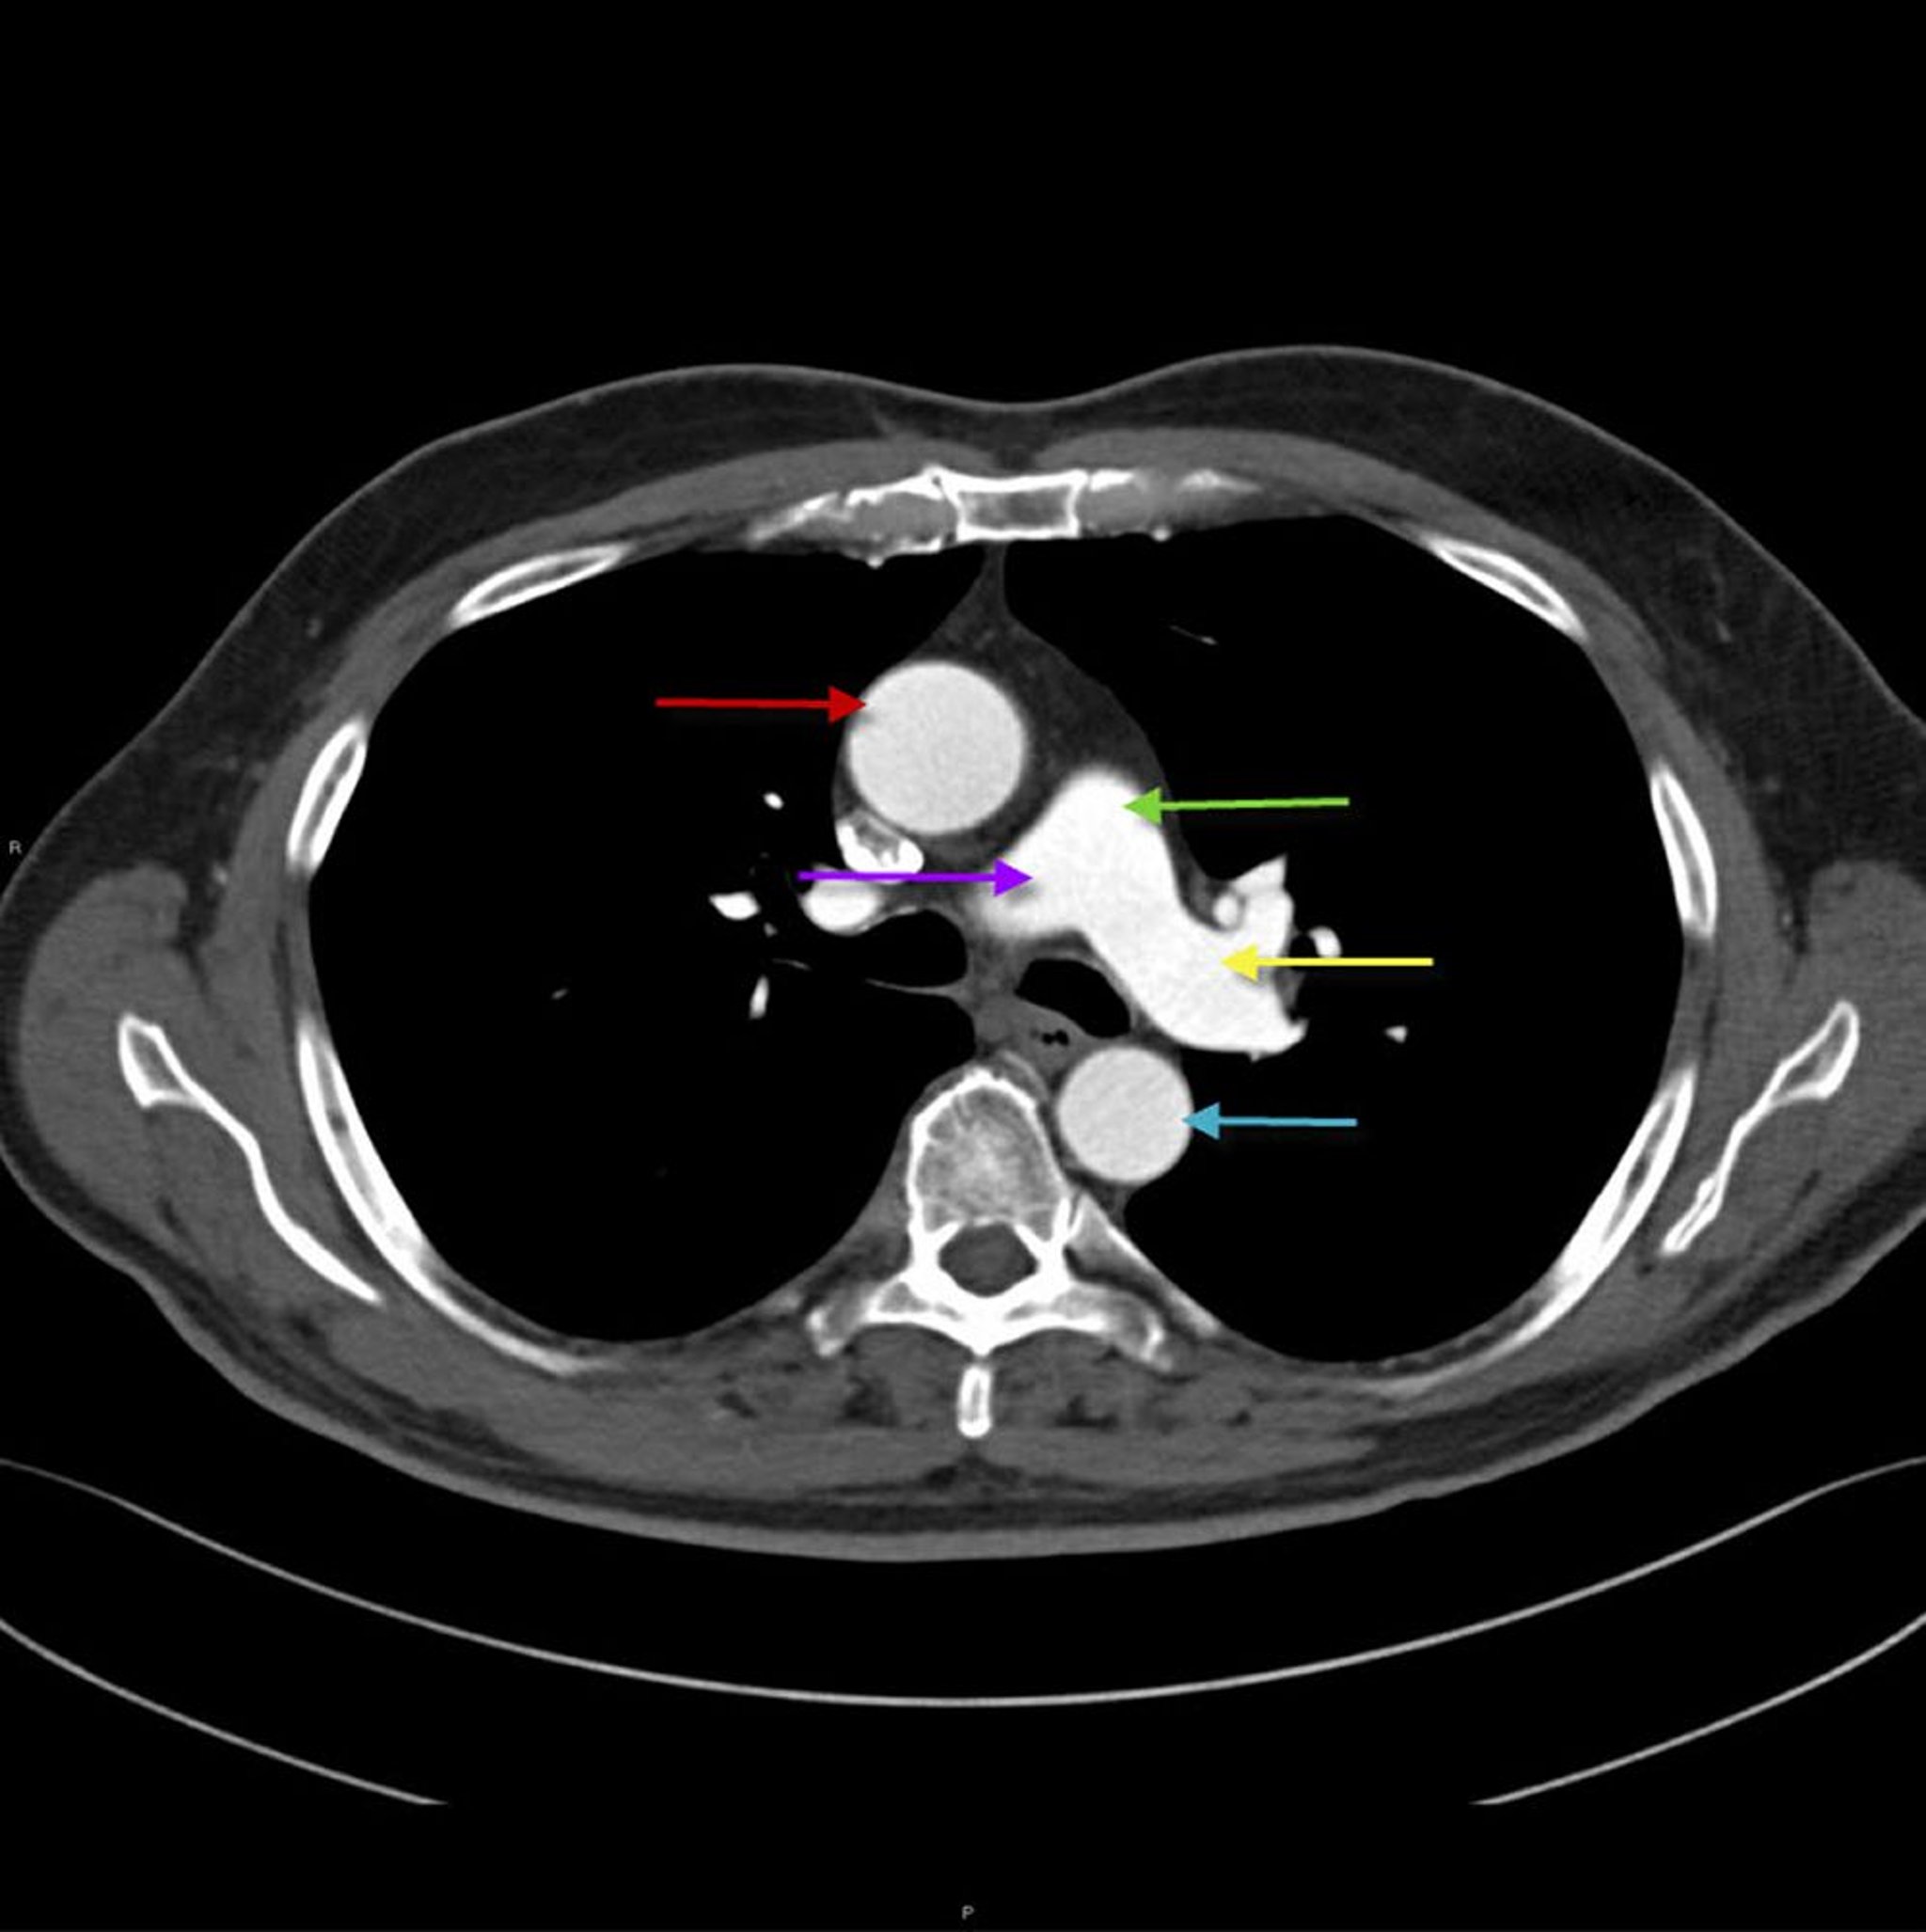

大動脈と肺動脈の構造を示した胸部CT画像

この画像には,胸部の上行大動脈(赤矢印)と下行大動脈が写っている。肺動脈幹(緑矢印)は右(紫矢印)と左(黄色矢印)の肺動脈に分岐する。